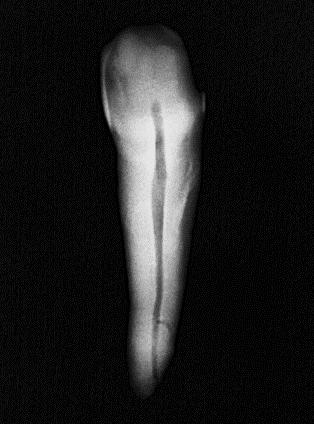

Se utilizaron 46 dientes extraídos unirradiculares superiores e inferiores con caries, pero sin compromiso radicular: sin ápices abiertos Los dientes con reabsorción radicular, fractura apical, caries que comprometieralaraízyápicesabiertosfueron descartados. Cada diente fue sometido a un proceso de limpieza por medio de ultrasonido para la remoción de cálculo y restos de tejido periodontal. Se le asigno un número a cada dienteysetomóunafotografíainicial(Figura 1).

Figura 1

FotografíainicialdeOD#27

Fuente: Pérez V, Salinas L. 2022.

Conductometría aparente

Es una de las etapas para obtener una medida de longitud, mediante una radiografía dentoalveolar, que corresponde a la distancia desde el punto de referencia coronal hasta el ápice radiográfico, definido como la porción

más apical del diente en una radiografía.

(Figura 2)

Figura 2

Conductimetría aparentedeOD#27

Fuente: Pérez V, Salinas L. 2022